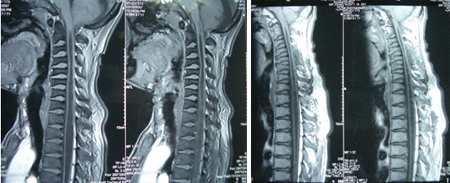

男性,35岁,自幼颅颈、双肩发育异常,双手、上肢肌萎缩3年,加重1月,伴走路不稳。查体:短颈、发髻低、双肩狭小畸形、脊柱侧弯,双上肢及躯干片状感觉障碍,双上肢肌力3-4级,远端更差伴双手爪形,双侧手指伸直困难,双侧病理征阳性。术前影像学资料显示:颅底凹陷、寰枕融合、颈椎生理曲度消失伴退行性改变,小脑扁桃体下疝入椎管伴脊髓空洞(达T8水平)。

术式:枕颈减压、枕大池成型、局限性椎板咬除减压、空洞穿刺引流术。术后可平稳行走,感觉障碍改善,术后半年肢体肌力改善。